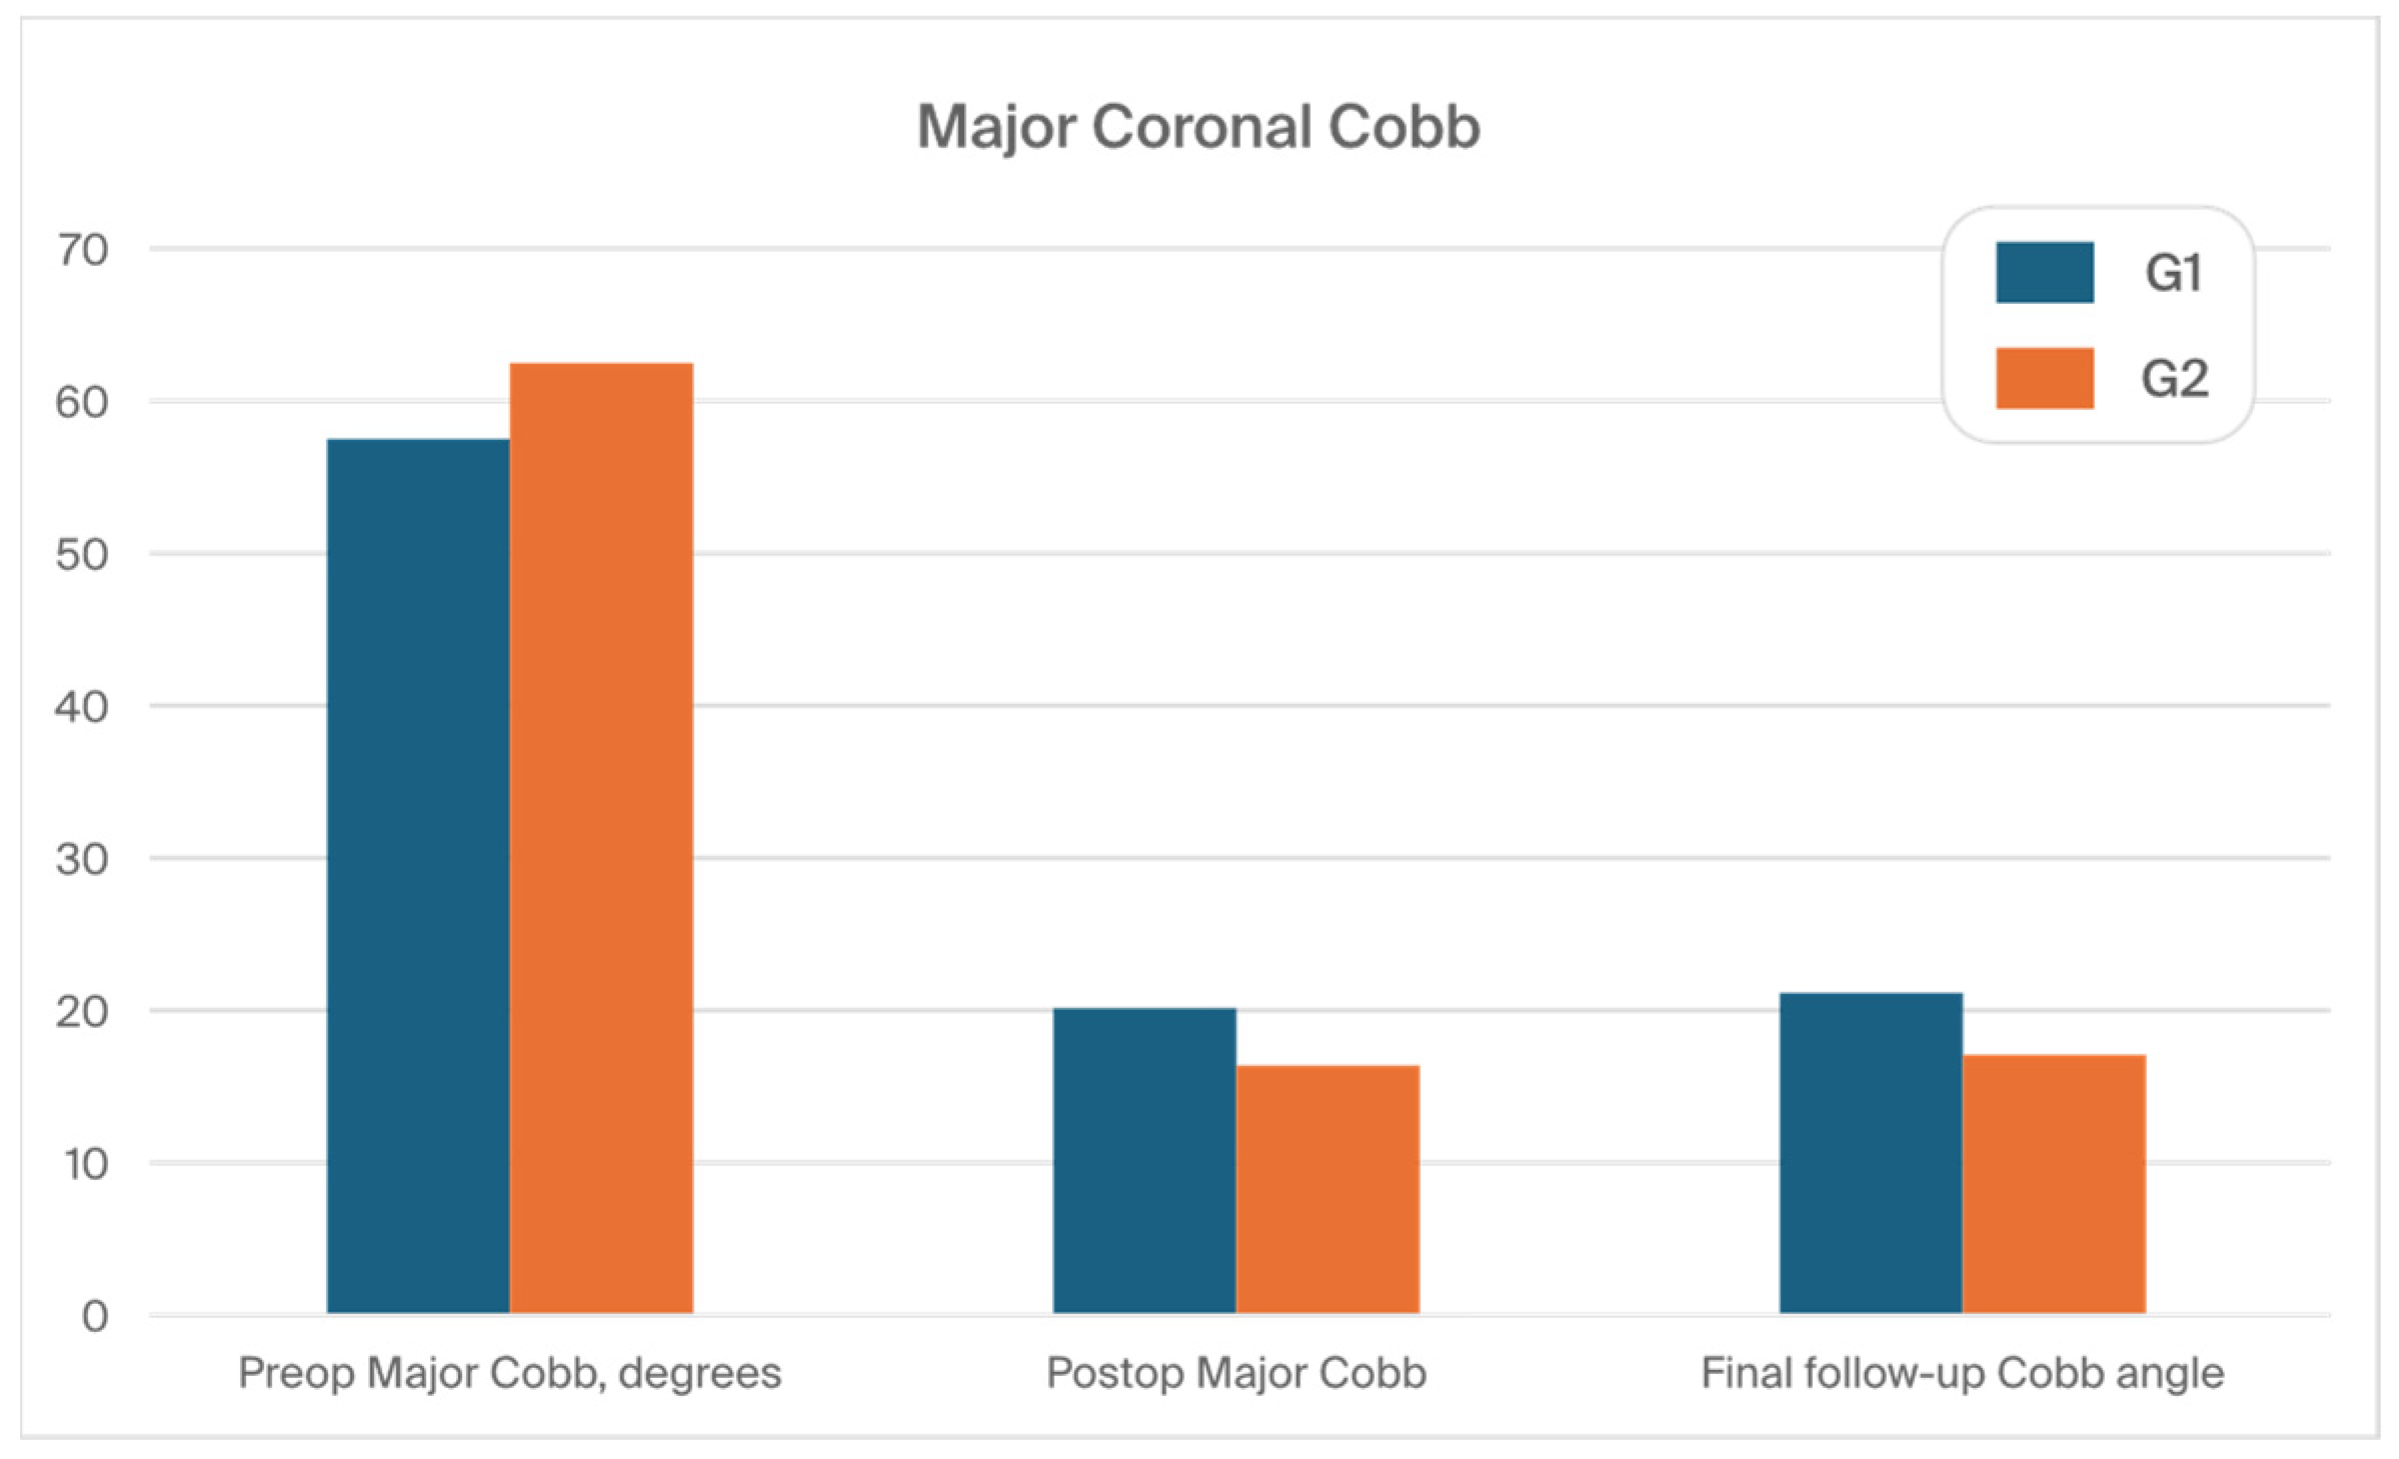

3.1. Clinical Characteristics and Radiographic Outcomes

| Preop major Cobb, degrees | 57.6 (11.9) | 62.5 (12.1) | 0.949 |

| Postop major Cobb | 19.8 (10.2) | 16.6 (8.2) | 0.001 |

| Final follow-up Cobb angle | 21.3 (9.2) | 17.1 (7.2) | 0.001 |

| % Cobb correction, postoperative | 69.8 (12.8) | 74.5 (11.2) | 0.001 |

| % Correction (FFU) | 61% (15) | 68% (14) | 0.001 |

| Loss of correction, degree | 5.9 (3.6) | 3.2 (3.2) | 0.001 |